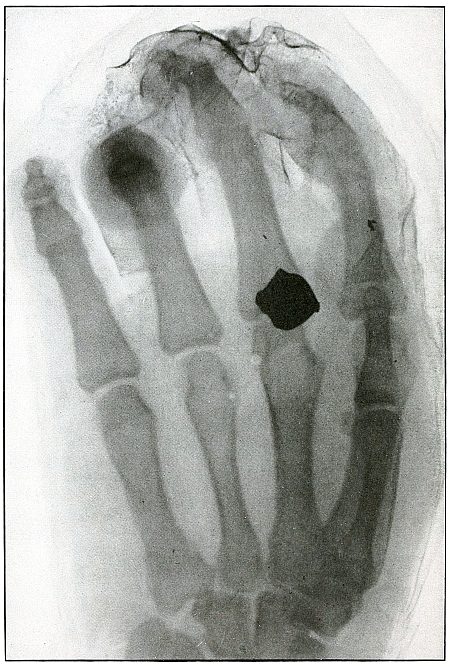

Plate 41.

[Pg 93]

Rifle—Plate 41.

UPPER EXTREMITY.

Gunshot Fracture of the Wrist.

Wound of entrance, posterior aspect of forearm over the lower end of

the radius, with the bullet ranging forward and slightly downward to

the wound of exit and covering with great laceration the anterior

aspect of the wrist joint.

The range was close, and the energy of the high velocity of the

missile was imparted to fragments, which, becoming “secondary

missiles,” emerged with the projectile to cause extensive laceration

and destruction of tissue.

The case was received for amputation in the second week, when a grave

degree of infection extended in a cellulitis to the elbow. The ulnar

nerve and vessels were intact, but the flexor tendons were almost

entirely destroyed.

The plate, made after several weeks, when infection was under control

and after the end of the radius and fragments of the carpus had been

informally removed, shows a rarefaction of the carpus and proximal

ends of the metacarpus, due to infection and disuse.

Frequent incisions and extension of drainage, with removal of detached

fragments, was continued for several months. The wound was closed in

the sixth month, with ankylosis and deformity of the wrist,

as shown in plate 42.